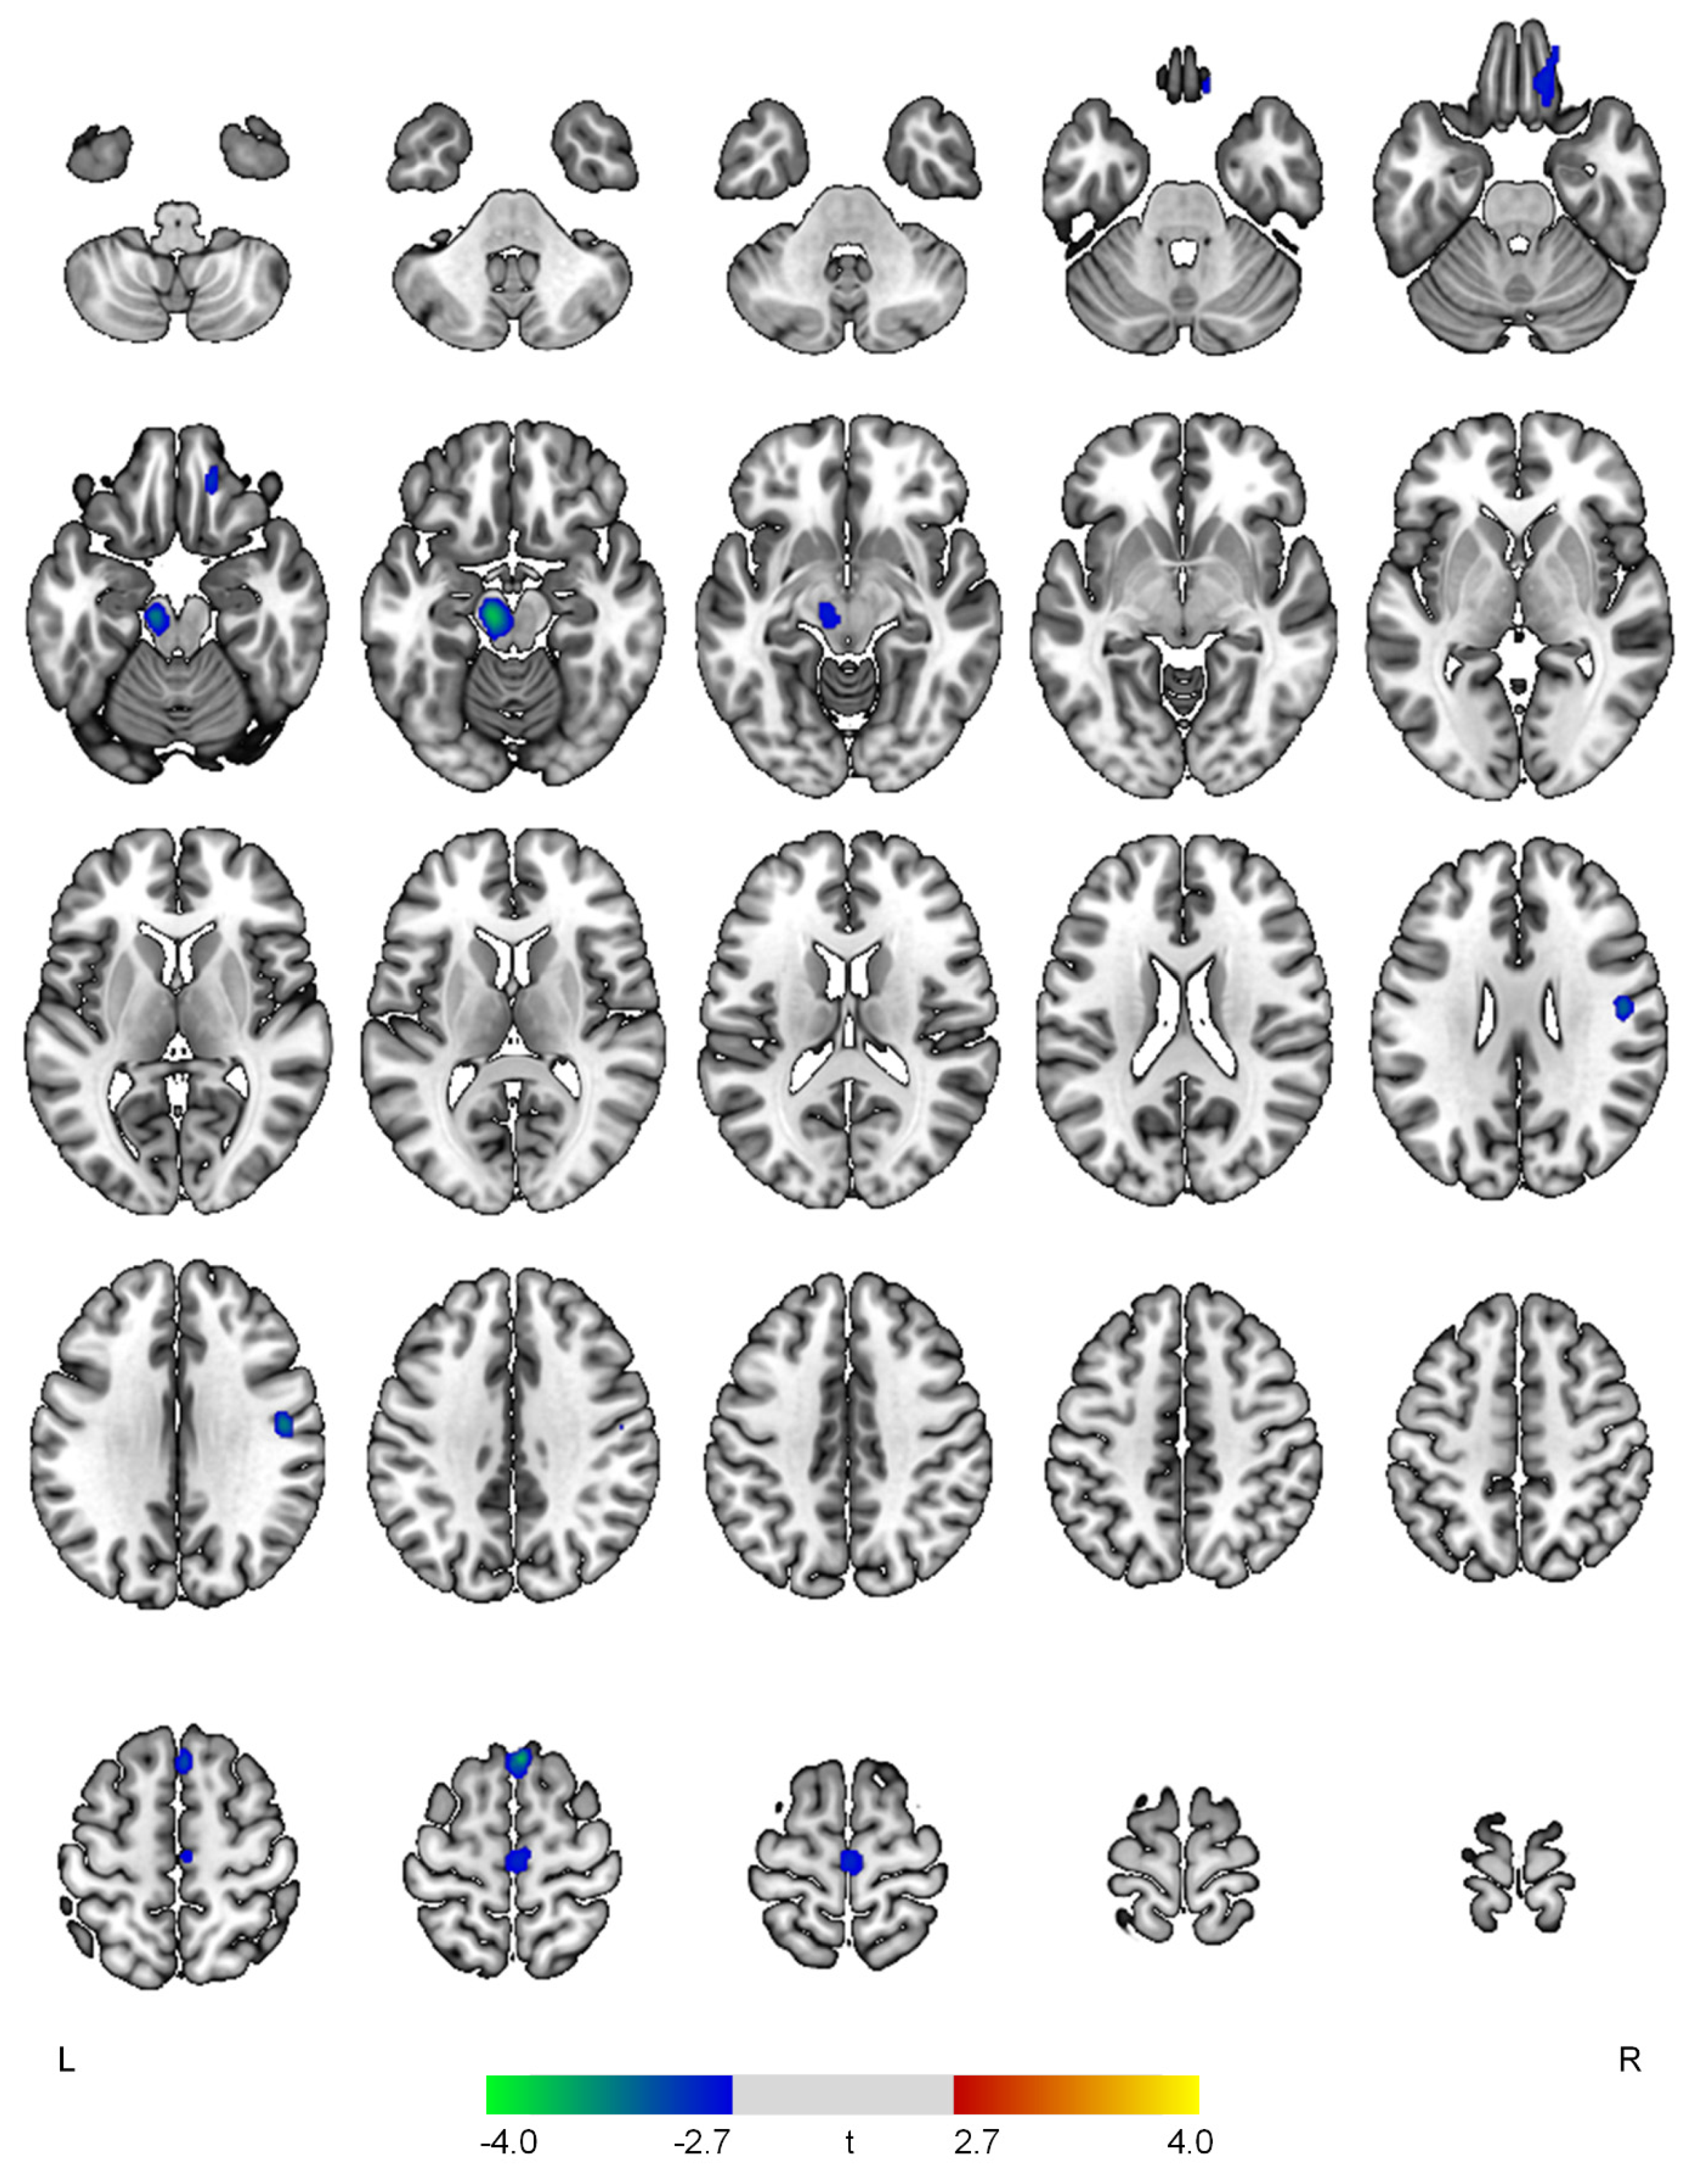

Figure 2.

Positive (red-yellow) or negative (blue-green) correlations between regional cerebral blood flow and the apathy domain in patients with early Alzheimer’s disease. The color bar represents t values at each voxel. L—left; R—right.

The severity of the apathy symptom domain was negatively associated with rCBF in the right superior frontal gyrus (t = 3.74, p < 0.001), left midbrain (t = 3.69, p < 0.001), right postcentral gyrus (t = 3.33, p = 0.001), right medial orbital gyrus (t = 3.01, p = 0.002), and right precentral gyrus (t = 2.89, p = 0.003) (Figure 2).

Higher apathy domain scores were associated with lower rCBF in the superior frontal, orbitofrontal, and pre/postcentral gyri and midbrain in our study. Consistent with our findings, decreased rCBF, hypometabolism, and atrophy of the superior frontal and orbitofrontal gyri have been consistently found in AD patients with apathy [6,7]. Moreover, reduced rCBF in the orbitofrontal gyrus may contribute to appetite loss in AD [22], further supporting the associations between apathy and eating abnormalities [14]. In early-onset AD, regional cerebral glucose metabolism in both the superior frontal and orbitofrontal gyri was negatively correlated with severity of the apathy domain [12]. These brain regions, which are closely involved in motivation, cognitive control, and decision making, may play important roles in apathy symptoms [23]. Although depression and apathy frequently share similar clinical manifestations, they have different neurobiological bases. While decreased rCBF in the superior frontal gyrus was found in relation to the affective domain, reduced rCBF in the orbitofrontal gyrus may be a distinct characteristic of the apathy symptom domain. AD patients with apathy demonstrated significantly lower rCBF in the postcentral gyrus and the superior frontal gyrus than those without apathy [24]. Moreover, lower functional connectivity between the planum polare and the precentral/postcentral gyri was found in apathetic patients with frontotemporal dementia and Parkinson’s disease (PD) compared to non-apathetic patients [25]. Functional deficits of the precentral and postcentral gyri in patients with apathy may be associated with a reduction in external stimuli perception and a subsequent impairment in motor response [25]. Apathy-related rCBF reduction in the midbrain has not been frequently found in previous AD research and may be one of the novel findings of this study. Increasing evidence from the preclinical and clinical studies has suggested that alterations in the midbrain structure and dopaminergic system may result in various NPSs in AD [26]. Similarly, PD patients with apathy also demonstrated lower activation of the prefrontal, striatum, amygdala, and midbrain regions in response to reward cues than those without apathy [27]. These results may underline potential links between functional deficits of the midbrain and apathy in AD patients.